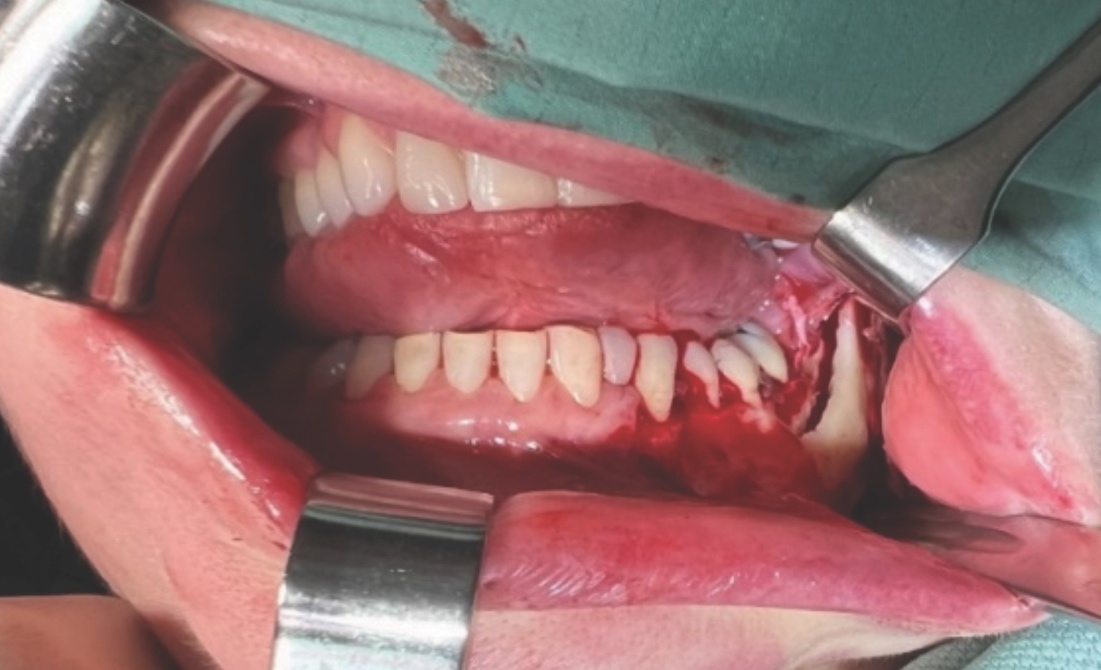

A unilateral sagittal split osteotomy was performed using piezosurgery to protect the nerve. The alveolar nerve, extending from the apical region of the left first and second molars to the mental foramen, was uncovered, and a meticulous dissection was performed to release it from the canal. Notably, rigid paste debris was observed in proximity to and within the nerve canal. The nerve exhibited signs of swelling and was surrounded by granulation tissue (Figures 4 and 5).

A thorough cleaning procedure ensued, followed by the repositioning of the two mandibular cortices, securing them in place with AO 5mm diameter bicortical screws, and without insertion of intermaxillary fixation (IMF) screws. Orthodontic brackets were used to stabilise the occlusion for six weeks (Figure 6).